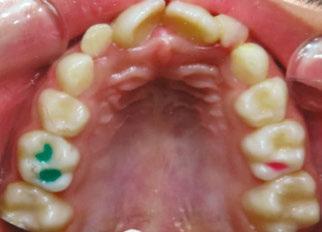

The following procedures were accomplished under general anesthesia on an outpatient basis — full mouth dental radiographs and a comprehensive oral exam. A complex odontoma was found to be the etiology of the noneruption of the maxillary right permanent central incisor (Figure 2). Since dental caries also was diagnosed, a full-mouth prophylaxis was completed. Dental caries was controlled, and teeth were restored. A 5 mm incision was made on the gingiva over the impacted maxillary right permanent central incisor, and two tooth-like structures were extracted from the right maxillary incisor area. A postoperative periapical radiograph was taken to confirm complete odontoma removal (Figure 3). Three interrupted sutures using 3-O chromic gut were placed.

At the postoperative consultation with the mother, we told her the tooth’s complete root formation might prevent its eruption. Orthodontic extrusion of the incisor was ruled out due to his behavior. A conservative approach with observation only was elected as treatment modality. This patient returned for follow-up appointments at ages 10, 11, 12, and 13. During all these visits, the maxillary right permanent central incisor had not erupted. At age 14, due to recurrent dental caries, the patient was taken to the local children’s hospital for dental rehabilitation again. During this second hospitalization, we noticed that the right maxillary central incisor was partially erupted into the oral cavity (Figure 4).

Figures 2 and 3: 2. Periapical radiograph of involved area taken in the operatory during initial dental rehabilitation under general anesthesia (left). 3. Periapical radiograph of involved area taken in the operatory during initial dental rehabilitation under general anesthesia immediately after odontoma removal (right)

Figure 4: Photograph of area at 14 years old during second rehabilitation under general anesthesia